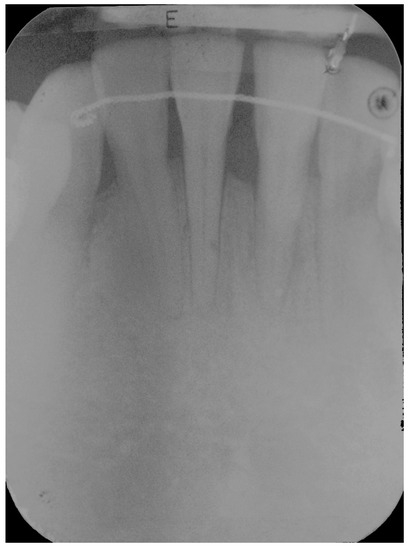

5. Materials and Methods